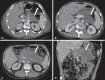

Acute pancreatitis is an inflammatory condition caused by intracellular activation and extravasation of inappropriate proteolytic enzymes determining destruction of pancreatic parenchyma and peripancreatic tissues. This is a fairly common clinical condition with two main presentations, namely, endematous pancreatitis - a less severe presentation -, and necrotizing pancreatitis - the most severe presentation that affects a significant part of patients. The radiological evaluation, particularly by computed tomography, plays a fundamental role in the definition of the management of severe cases, especially regarding the characterization of local complications with implications in the prognosis and in the definition of the therapeutic approach. New concepts include the subdivision of necrotizing pancreatitis into the following presentations: pancreatic parenchymal necrosis with concomitant peripancreatic tissue necrosis, and necrosis restricted to peripancreatic tissues. Moreover, there was a systematization of the terms acute peripancreatic fluid collection, pseudocyst, post-necrotic pancreatic/peripancreatic fluid collections and walled-off pancreatic necrosis. The knowledge about such terms is extremely relevant to standardize the terminology utilized by specialists involved in the diagnosis and treatment of these patients.